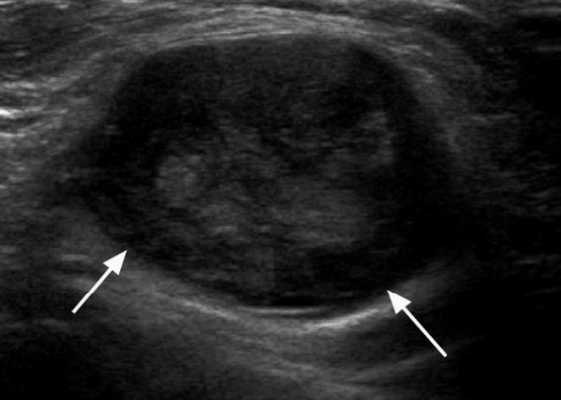

Практически во всех случаях дифференцировали лимфатический узел Кютнера (югулодигастральный), расположенный на границе средней и верхней трети шеи. Выявляемые лимфатические узлы имели размеры от 0,5 х 0,2 см до 2,3 х 0,8 см. УЗ-оценку производили после полипозиционного осмотра и нахождения самой длинной горизонтальной оси, что и принимали за максимальный поперечный диаметр. Большая часть лимфатических узлов (187) имели овальную форму с соотношением поперечного/переднезаднего более 1 (рис. 1 - 3). Тенденцию к округлению имели 30 лимфатических узлов, соотношение поперечного/переднезаднего приближалось к 1.

Рис. 1. УЗ-томограмма увеличенного реактивно измененного лимфатического узла: а - на фоне аденовирусной инфекции, б - после проведения противовоспалительного лечения

Рис. 2. Эхографическое изображение непальпируемого югулярного лимфатического узла на фоне остаточных явлений после перенесенного фарингита.

Рис. 3. Эхографическое изображение непальпируемого югулярного лимфатического узла без четкой клинической симптоматики воспалительного процесса в области головы и шеи.

Мы установили, что, как правило, более округлая конфигурация лимфатического узла при его размерах, превышавших 10 мм, сопровождалась небольшими болевыми ощущениями, и более выраженной простудной (воспалительного характера) симптоматикой. Лимфатические узлы менее 10 мм чаще всего плохо пальпировались, либо вообще не выявлялись пальпаторно. Во всех случаях эхографически хорошо дифференцировался гипоэхогенный кортикальный слой и широкое, средней или чуть ниже средней эхогенности изображение области ворот лимфатических узлов. Четкость дифференциации составных частей лимфатического узла была снижена при размерах менее 5 мм. Мы отмечали различную толщину гипоэхогенного изображения области коры лимфатического узла: от очень широкой - при выраженности или прогрессировании воспалительного процесса, до узкой - на фоне положительной динамики.